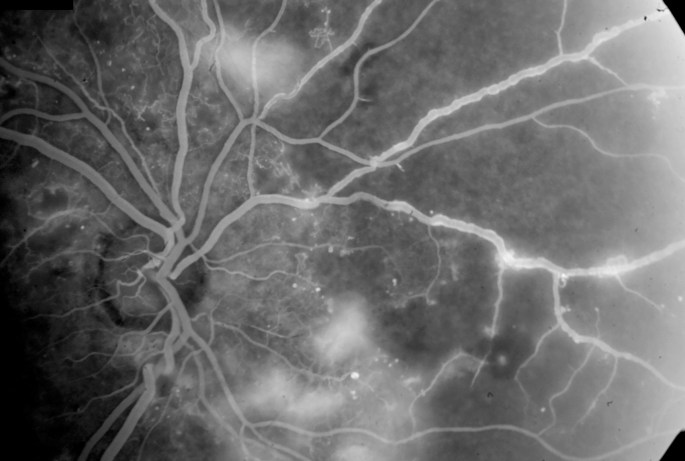

In the early 1990’s I wrote my own electronic medical record system. I also developed my own very high resolution digital fluorescein angiogram system (FA) and I started to look at the images of the diabetic patients. I became about 70% accurate in the ability to look at the FA images and tell the patient what their soda consumption was. There was focal constriction of the pre-capillary arterioles that I noticed as well as the size of the foveal avascular zone and general capillary drop out on the images. Further analysis of the electronic medical records showed a correlation of soda drinking to hypertension, renal failure and heart disease. Now as retina specialists we tend to use intraocular steroid and anti-vegf injections for these patients, while some may be reversed by a diet change of eliminating sodas first rather than having injections, with cost and the complications of drug intervention. The risk is minimal to stop the sodas, the benefit may be avoiding costly drug use and organ damage. There are multiple patients with advanced renal failure that were drinking multiple liters of diet sodas and when they quit drinking them, their renal failure progression stopped or started to reverse to the consternation of the nephrologist. The soda “quitters” had about a 10-15 point drop in the average BP without a change in the medications.